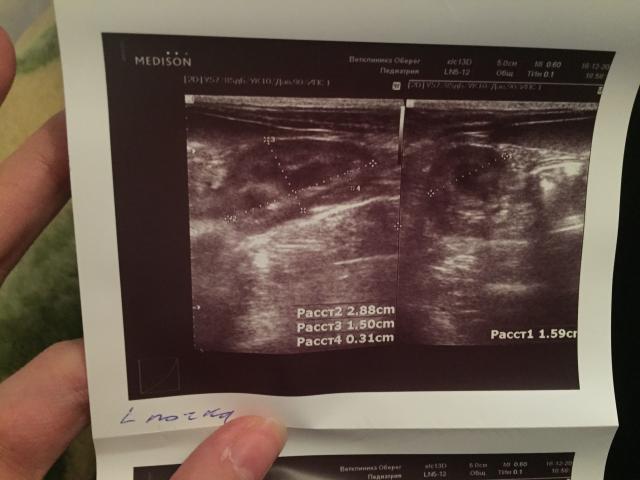

Если можно, то немного подробнее. На основании чего вам поставили такой диагноз, только на основании проведенного УЗИ? Может быть, собаке брали какие-то анализы? Если да, то выложите, пожалуйста, здесь их результаты. Если только данные УЗИ, то это разговор ни о чем (я имею ввиду панкреатит). Гастрит по данным УЗИ вообще не ставят.

К сожалению, ничего не могу рассмотреть. Попробуйте сами прочесть описание с фото. Если сможете, сделайте снимок более качественным. Или можно снять крупнее по частям. Может быть, тогда буквы будут видны более четко.

Спасибо, фотографии четкие. Я все прочитал. Как я и думал, там и "не пахнет" никаким гастродуоденитом, а тем более, панкреатитом.